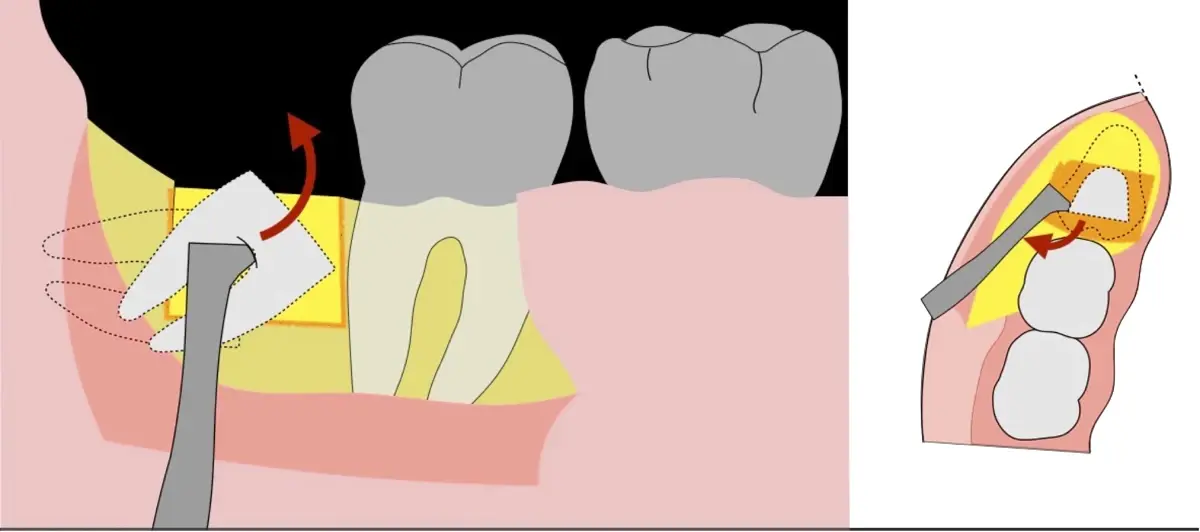

Figura 4. Demarcación de la zona de osteotomía con insertos de corte recto y/o angulado a nivel oclusal. Vista frontal (a). Vista oclusal (b).

Figura 5. Fractura y eliminación oclusal del fragmento óseo de la porción coronal oclusal.

Figura 6. Demarcación y fractura de la zona de osteotomía a nivel vestibular con inserto aserrado recto y/o angulado.

Figura 7. Eliminación del fragmento vestibular.